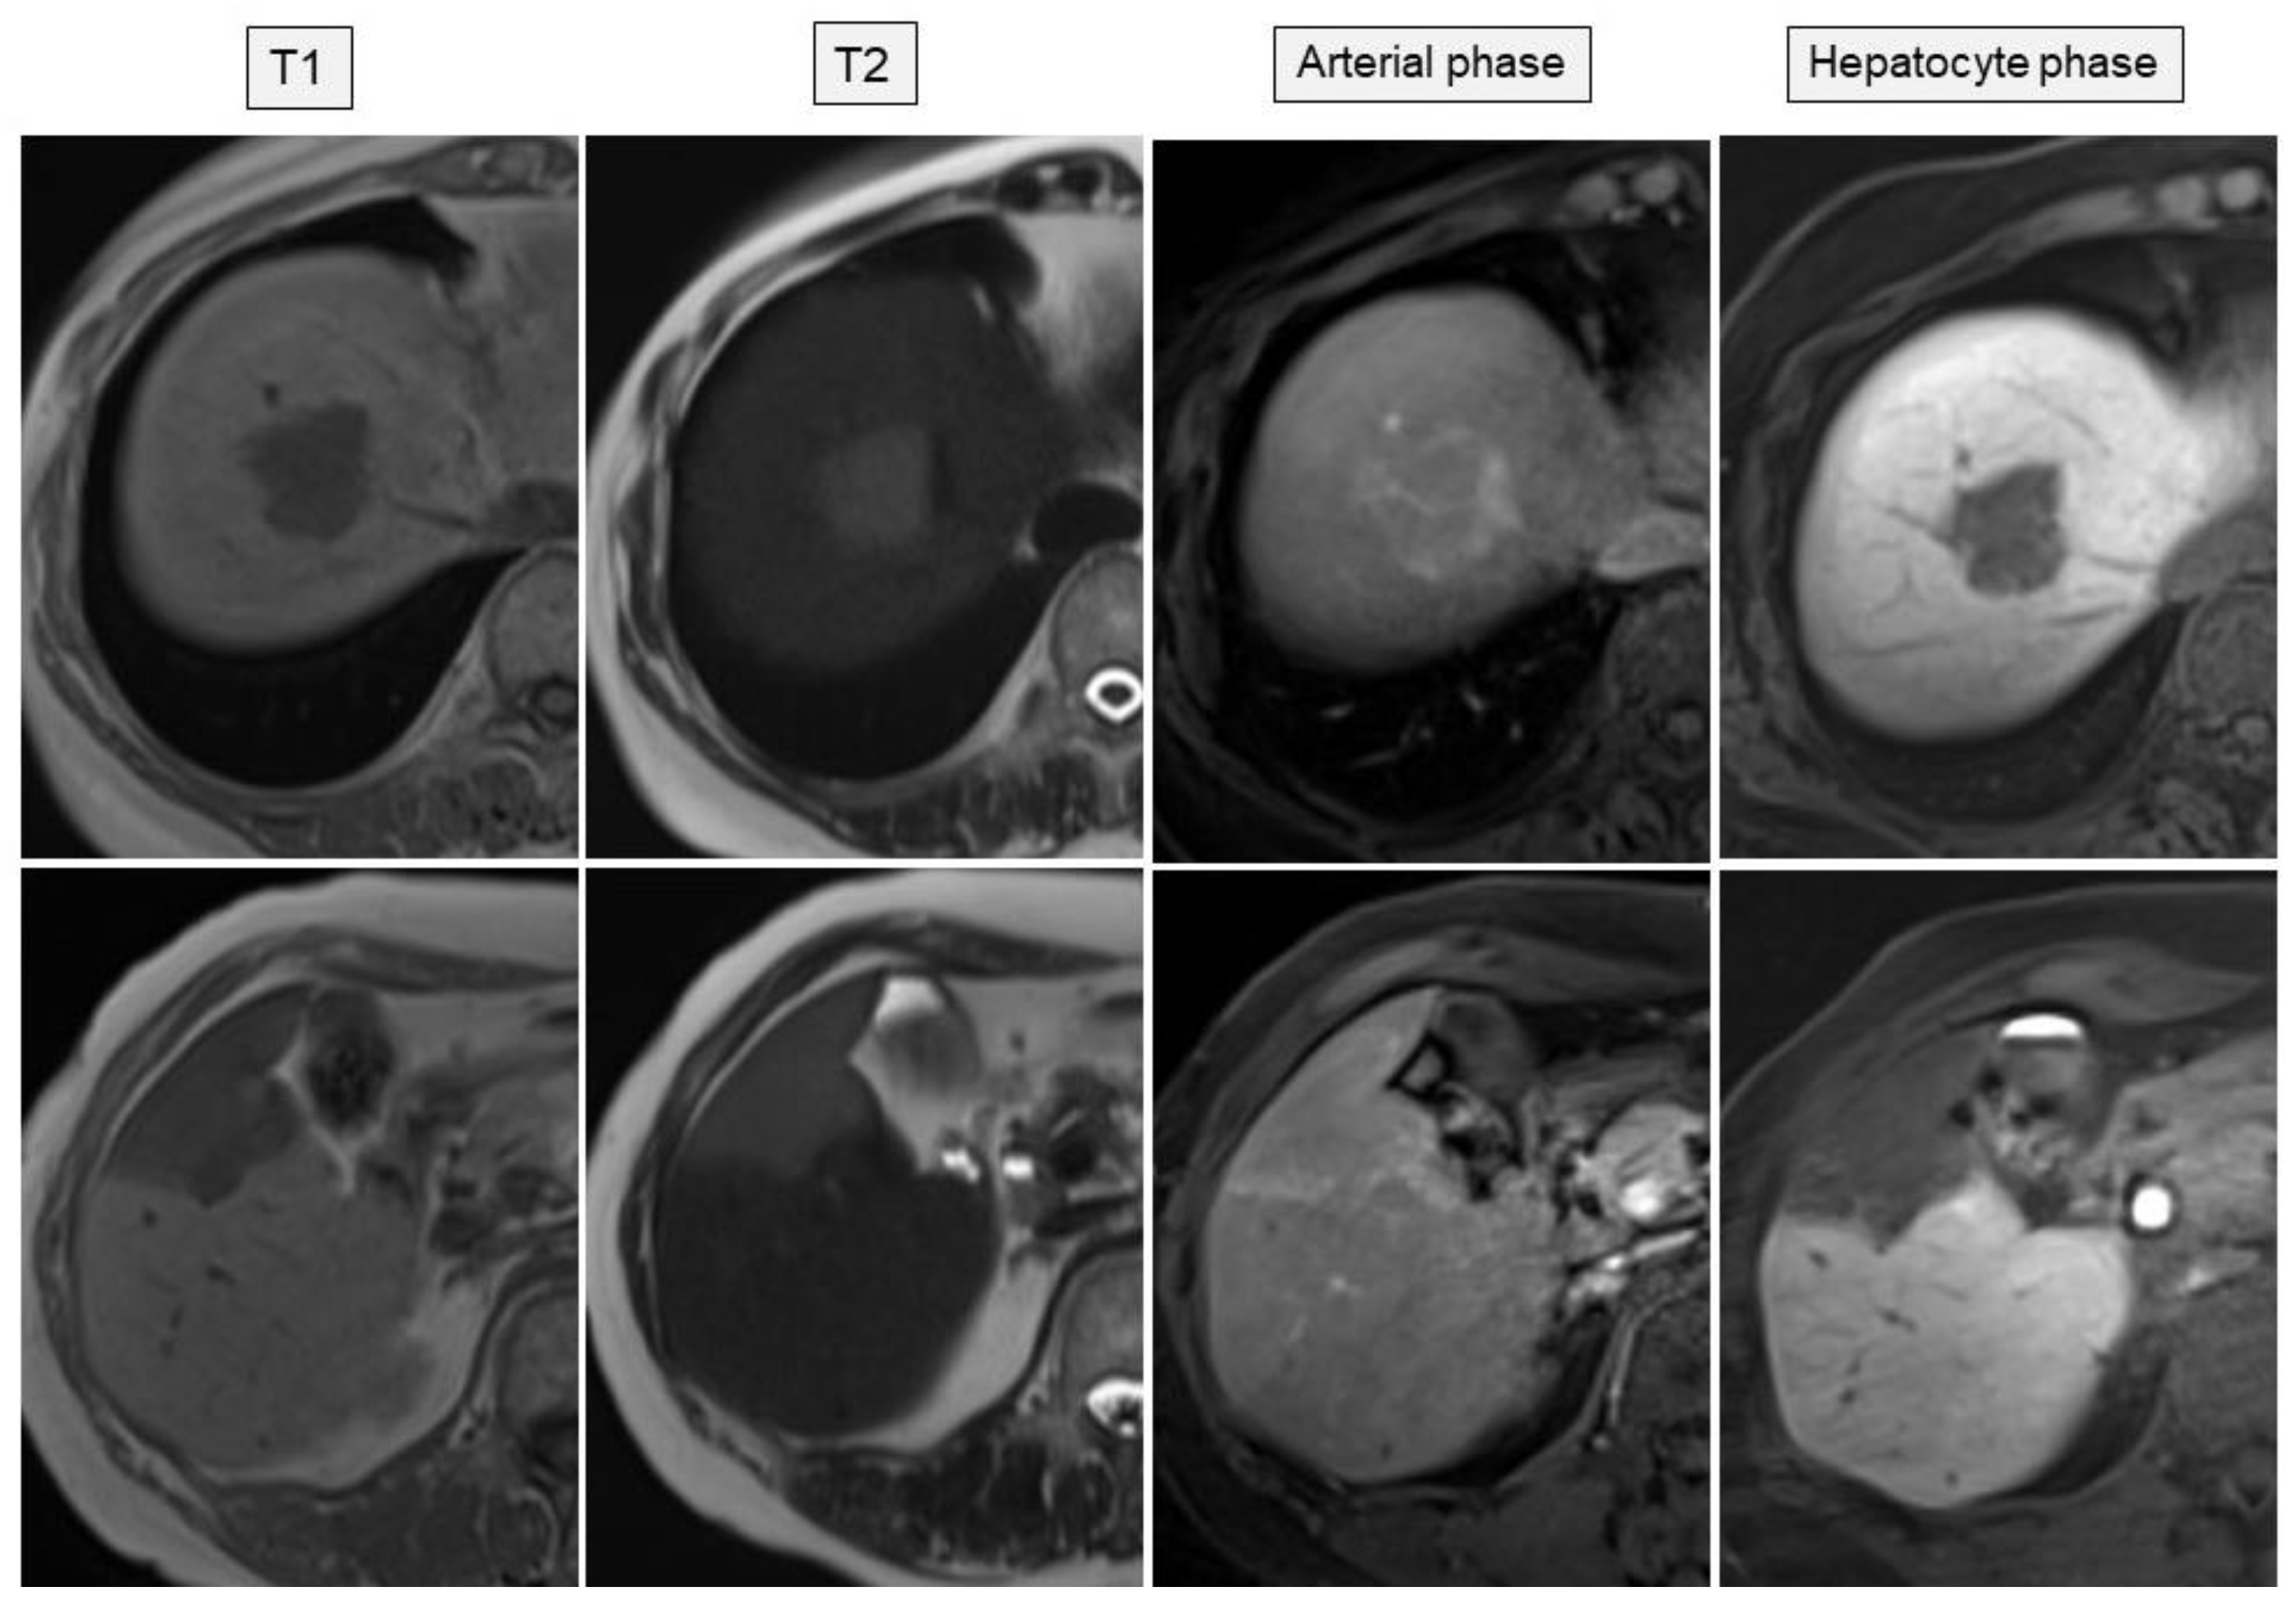

| MRI | T1-weighted: low intensity, T2-weighted: high intensity | T1-weighted: low intensity, T2-weighted: high intensity | T2-weighted: high intensity |

| Gd-EOB-MRI | Enhanced in arterial phase, low intensity in hepatocyte phase | Enhanced in arterial phase, low intensity in hepatocyte phase | Enhanced in arterial phase, low intensity in hepatocyte phase |